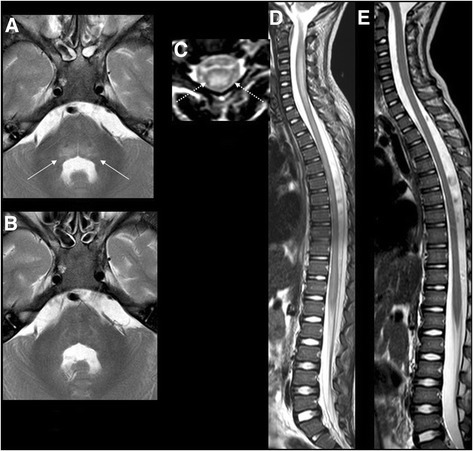

- MRI: spinal cord lesion, largely restricted to gray matter, spanning one or more spinal segments

(Spinal cord lesions may not be present on initial MRI if performed within the first 72 hours of onset of acute limb weakness.)